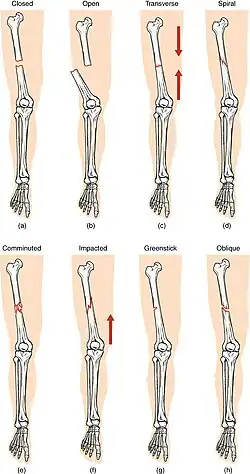

Compare healthy bone with different types of fractures:

(a) closed fracture

(b) open fracture

(c) transverse fracture

(d) spiral fracture

(e) comminuted fracture

(f) impacted fracture

(g) greenstick fracture

(h) oblique fracture

• Linear fracture – a fracture that is parallel to the bone's long axis

• Transverse fracture – a fracture that is at a right angle to the bone's long axis

• Oblique fracture – a fracture that is diagonal to a bone's long axis (more than 30°)

• Spiral fracture – a fracture where at least one part of the bone has been twisted

• Impacted fracture – a fracture caused when bone fragments are driven into each other